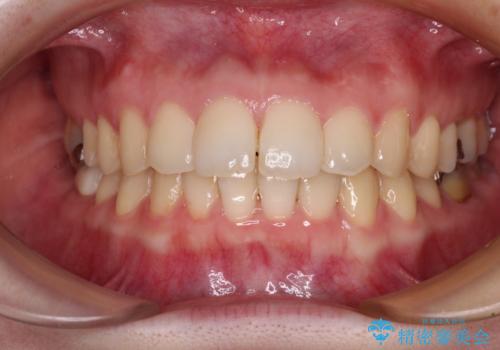

デコボコ歯列をきれいに インビザラインによる矯正治療

- 上下歯列全体のデコボコを気にして来院された患者様です。

主に下顎歯列全体の後方移動とIPR(歯と歯の間を削る)によってデコボコが解消するように設計し、インビザラインにより治療を行うこととしました。

1年半程度で終了するのではないかと予想しましたが、途中1年以上の来院がなく、トータルで3年の時間がかかってしまいました。

前歯のデコボコはより改善することが望ましい状態でしたが、患者様の希望により終了することとなりました。